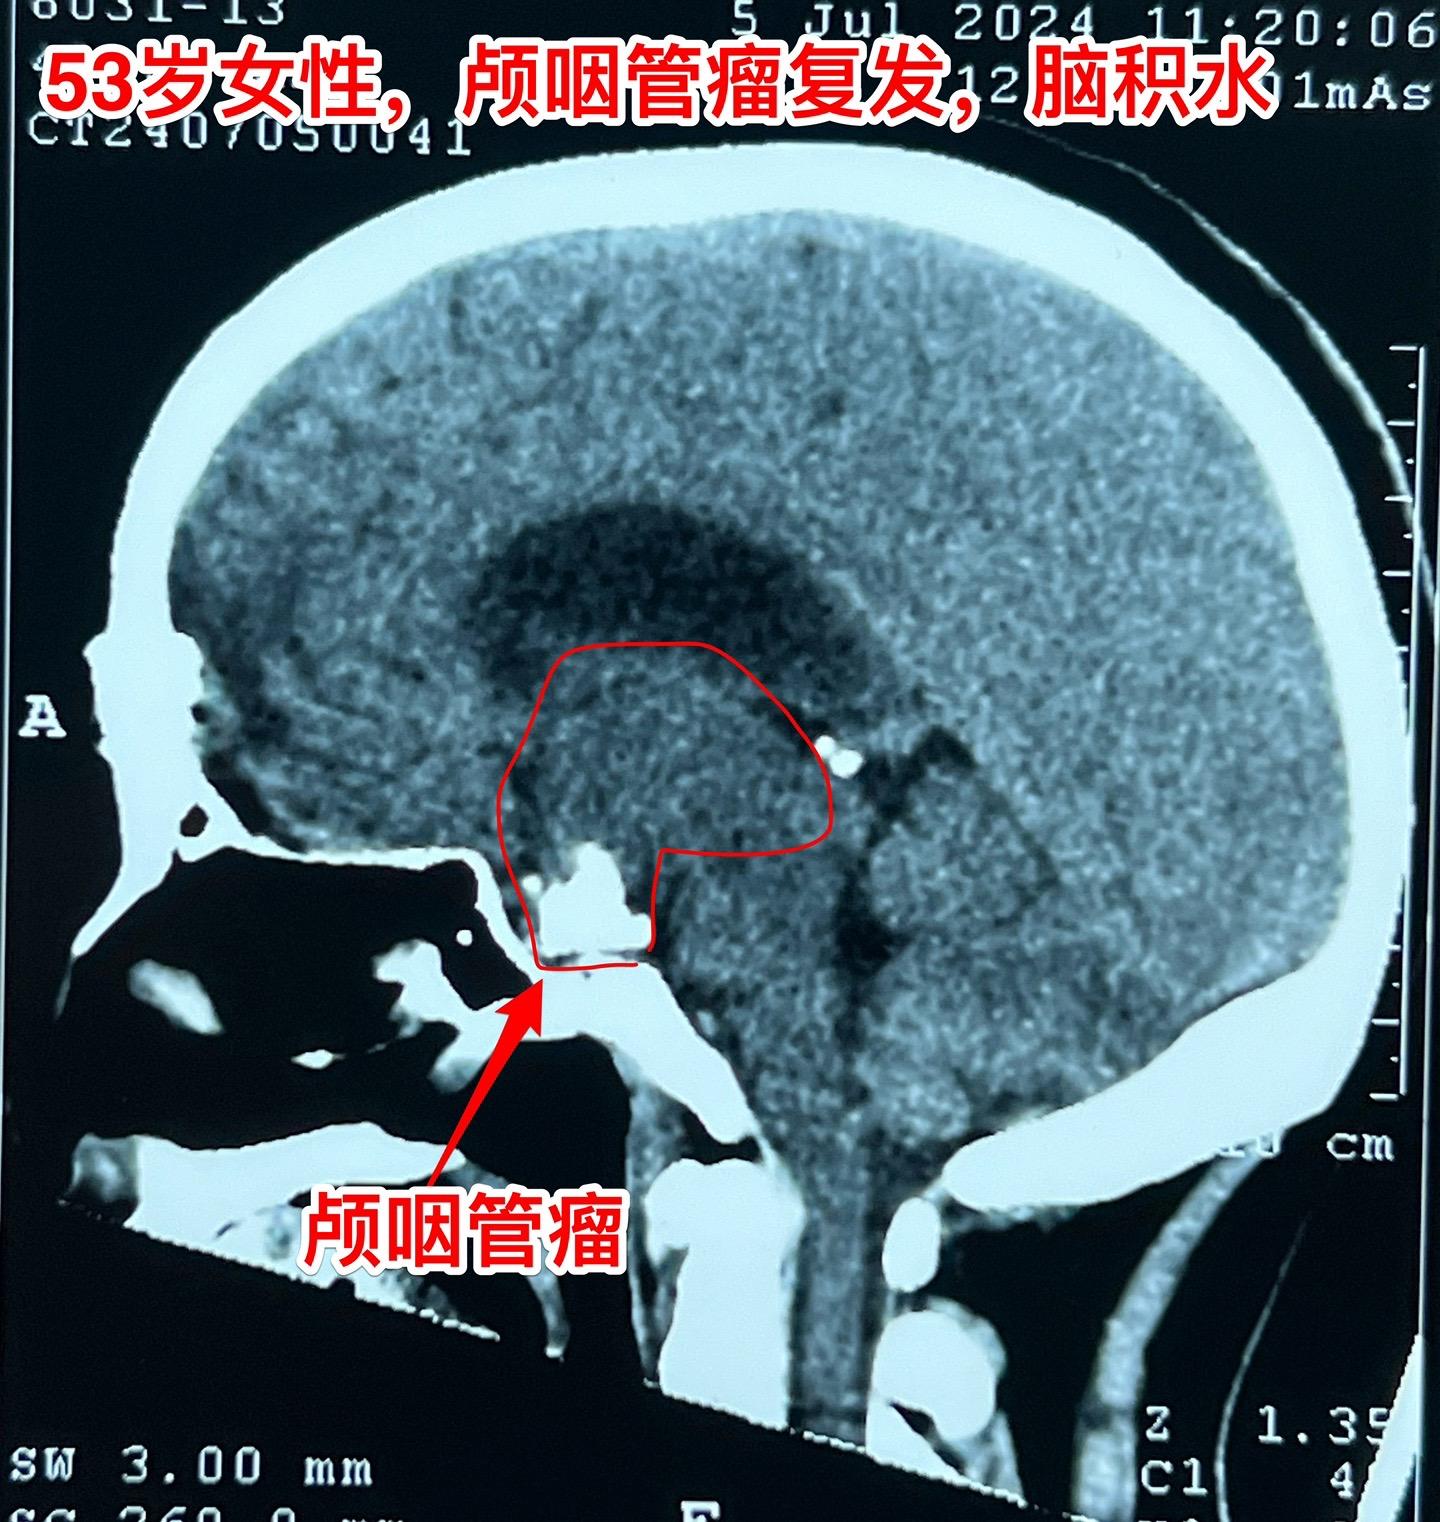

69岁发现颅咽管瘤还能作手术吗?69岁的南通市老人近半年出现记忆力差、糊涂。4月份出现尿失禁,到医院检查才发现病根儿是颅咽管瘤,肿瘤体积大,导致了脑积水。第一步在当地医院先作了脑室-腹腔分流术,治疗脑积水,尿失禁的症状有改善。 但是老人的身体很虚弱。还不能下地行走。这样的身体状态是不能承受切除颅咽管瘤这样的大手术的。 老人的女儿随后和我加后,我给予老人补充激素后,老人的身体状况才逐步改善,慢慢地能下地走路了。 不能不佩服这家人的勇气和爱心[强][强]! 2024-06-12 06:07